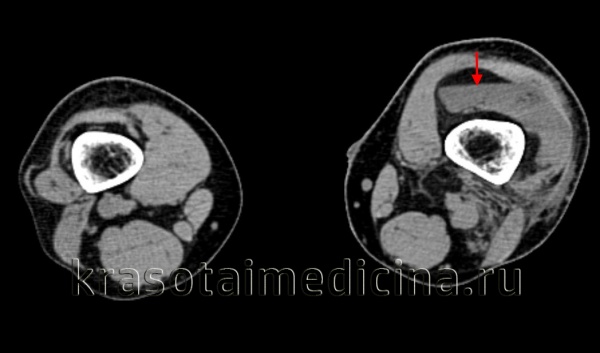

КТ коленных суставов. Уровень жидкости в супрапателлярной сумке слева у пациента с переломом мыщелков левой большеберцовой кости.

При первой степени патологии (объем излившейся крови до 15 мл) сустав незначительно увеличен в объеме. Преобладают симптомы основной травмы (обычно ушиба коленного сустава). Боли – локальные в области повреждения, распирающих болей в суставе нет. Опора на ногу свободная или несколько ограничена. При второй степени гемартроза (объем излившейся крови до 100 мл) сустав увеличивается в объеме, становится шарообразным, его контуры сглаживаются.

Во время пальпации определяется флюктуация. При значительном скоплении крови в коленном суставе наблюдается заметное выбухание по переднебоковым поверхностям снаружи и изнутри от надколенника. При продолжающемся кровотечении и третьей степени гемартроза (объем излившейся крови более 100 мл) кожа может становиться синюшной, а мягкие ткани – очень тугими, напряженными. В некоторых случаях отмечается повышение местной температуры.